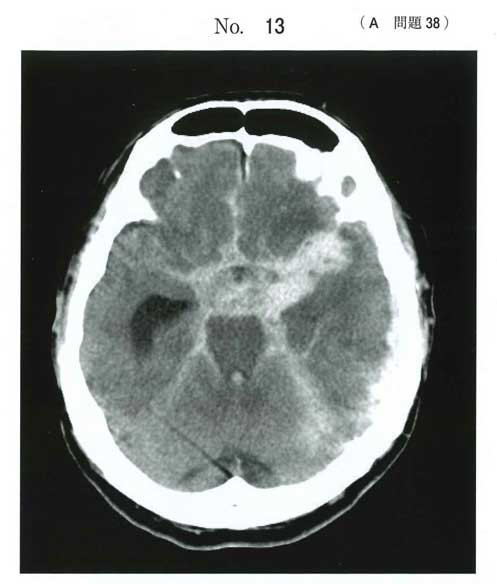

画像診断 別冊No. 13の頭部単純CTでは、脳槽(特に左鞍上槽からSylvius裂)にかけて、出血によると思われる高吸収域が認められる。

診断名 脳動脈瘤破裂によるくも膜下出血、左末梢動眼神経麻痺

原因となる脳動脈瘤は内頚動脈-後交通動脈分岐部に存在する可能性が最も高い。

CTではbasal cisternから左Sylvian fissureにくも膜下出血を認め、warning signとして左動眼神経麻痺を示唆する所見があることから、左内頚動脈後交通動脈分岐部動脈瘤破裂が最も考えらる。

SAHの中で左寄りに点状の低吸収域(filling defect sign)があるかな?

画像だと、MCAだったらもっと外側